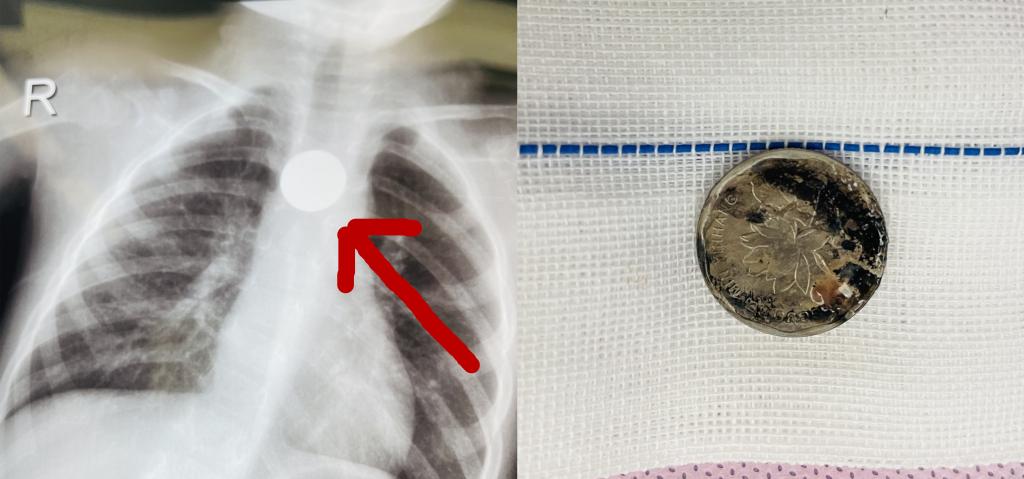

近年来,交大二院小儿外科时常遇到各类消化道异物患儿前来就诊,有的误吞硬币卡在胃里,有的误食磁力珠最后导致消化道穿孔,有的误食玻璃弹珠,有的误食纽扣电池,误食各种“核”后卡在消化道的患儿更是层穷不出。在此,医生也提醒广大宝爸宝妈,一定要看好小朋友,尤其是“什么都往嘴里放”的低龄幼儿。稍不留神,就可能造成不可逆的后果。